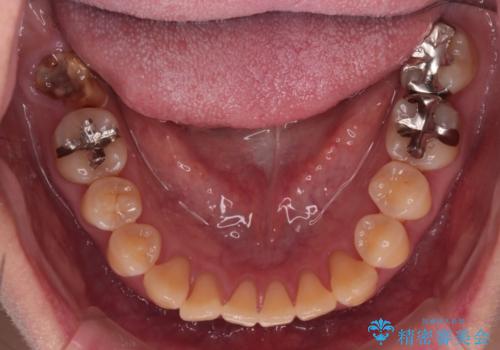

- 上の前歯の捻れと、前歯で物が噛めないことを主訴に来院されました。

前歯の翼状捻転とオープンバイト傾向だったため、インビザラインにて矯正を行いました。右下の奥歯は保存不可だったため、抜歯を行いインプラントにて修復を行なっています。

翼状捻転はインビザラインでは苦手とする動きですが、ここまで綺麗に治すことができました。